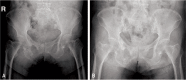

Materials and methods: Fifteen patients diagnosed with pelvic insufficiency fractures were evaluated retrospectively. All patients had osteoporosis with mean lumbar T score of -3.9 (range, -3.1 to -6.4) and the mean age was 76.5 years. In all cases, simple radiography and computed tomography was used for final diagnosis; additional magnetic resonance imaging and technetium bone scans were used to confirm the diagnosis in 2 and 6 patients, respectively. Initial conservative treatment was used in all cases; treatment with PTH was applied in 5 cases. Radiological follow-up was done every 4 weeks up to 6 months and every 3 months thereafter. Symptom improvement was measured using visual analogue scale (VAS) score.

Results: Fractures were located: i) sacrum and pubis (9 cases), ii) isolated sacrum (4 cases) and iii) isolated pubis (2 cases). One case showed fracture displacement and pain aggravation at 4 week follow-up which was treated with percutaneous sacro-iliac fixation using cannulated screws. Duration of bone union was significantly shorter in the patients who used PTH (P<0.05). VAS scores were also lower in the group treated with PTH; however, statistical significance was not reached.